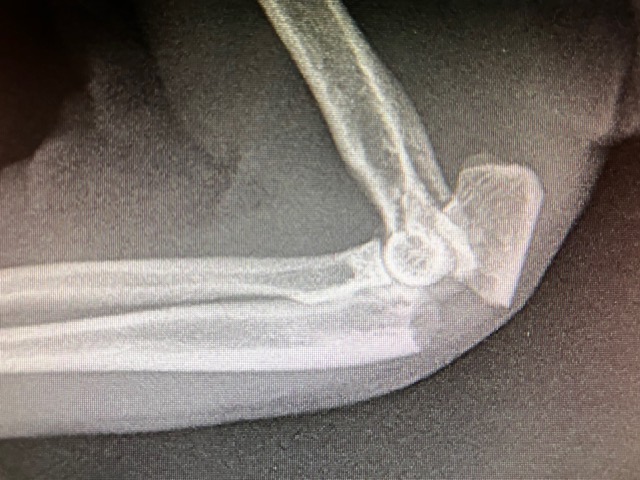

Un examen radiographique est réalisé sous légère sédation et après administration d’antalgique.

Le coude est une articulation complexe s’appuyant sur 3 os différents : L’extrémité distale de l’Humérus, avec le condyle huméral. Dans les chocs et fractures du coude, il est important de bien inspecter et contrôler les Condyles, et de vérifier qu’un trait de fracture n’existe pas à cet endroit. On contrôle cela sur une radiographie de face, si nécessaire on complète par un cliché en position oblique. L’avant bras est constitué de 2 os : le radius et l’ulna ( ou cubitus ). Ces 2 os s’articulent avec le condyle huméral, l’ulna a une forte échancrure pour accueillir la zone inter-condylienne, il forme aussi la pointe du coude.

Dans notre cas, la Fracture – bien visible sur la radiographie de profil – est localisée sur l’Ulna, au niveau de l’articulation, dans la zone de l’échancrure sigmoïdienne. La Pointe du Coude – appelée l’Olécrane – est basculée en arrière. En effet sur son extrémité s’accrochent les tendons des puissants muscles triceps du bras, qui permettent le mouvent d’extension de ce dernier. Le triceps déplace donc en arrière et vers le haut l’olécrane fracturé. Cette fracture est simple, transverse, légèrement oblique. Le Radius est intact, en place. Dans ce type de fracture, le choc traumatique génère souvent une luxation associée du coude, et notamment un arrachement important et grave des ligaments du coude : on parle alors de Fracture de Monteggia. Dans notre cas la fracture est plus simple, les dégâts ne semblent toucher que l’échancrure sigmoïdienne ulnaire.